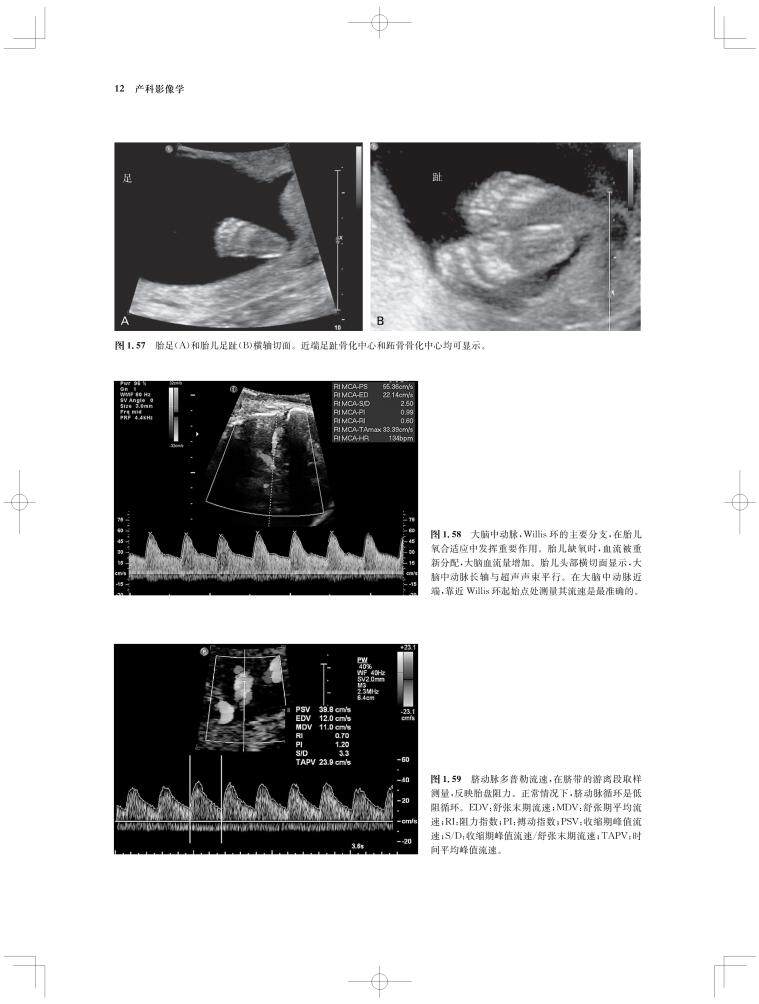

内容涵盖了胎儿宫内疾病的所有病种,从疾病的概述、流行病学、病因学、病理生理学,到临床表现、各类影像学技术的诊断和鉴别诊断,再到产前、产后的治疗和干预手段,都做了全面介绍,重点阐述了疾病的超声、X线、CT、MRI、PET、CT等影像学表现,以及诊断与鉴别诊断,并辅以大量标准化的影像学图片,图文并茂。

《产科影像学——胎儿诊断和监护》是Elsevier(Saunders)出版的“Expert Series”之一,由国际最顶尖的妇产科、生殖科、母胎医学和影像学专家共同编写,代表着该领域最顶尖的水平。书中配有大量典型影像图片,内容丰富全面,编写理念先进,侧重于疾病的影像学征象分析及鉴别诊断和诊断流程的制定,从临床思维上进行了更新;同时兼顾临床和病理医师,重点内容以列表、提要、要点的形式进行总结,提纲挈领,方便读者阅读、记忆。对于每天不断进行诊断与鉴别胎儿疾病的影像工作者、病理科和临床医师而言,具有重要的参考价值。